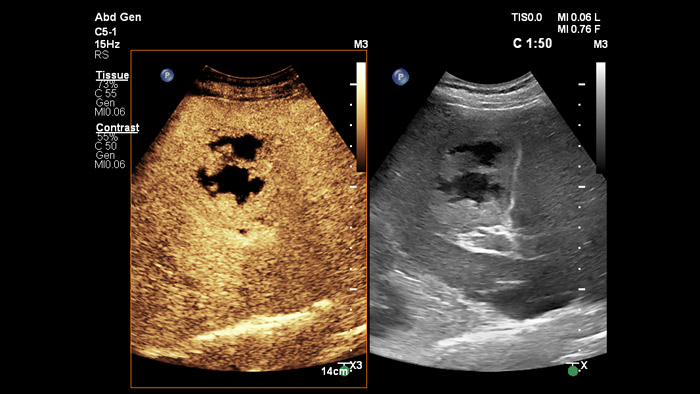

Ultraschall-Kontrastmittel können die Rolle des Ultraschalls verändern: Verstärkungsmuster von Leberläsionen können von Klinikteams in Echtzeit untersucht werden. Bei Ultraschallgeräten von Philips sind kontrastmittelverstärkte Ultraschalluntersuchungen nahtlos in den Standardablauf integriert.